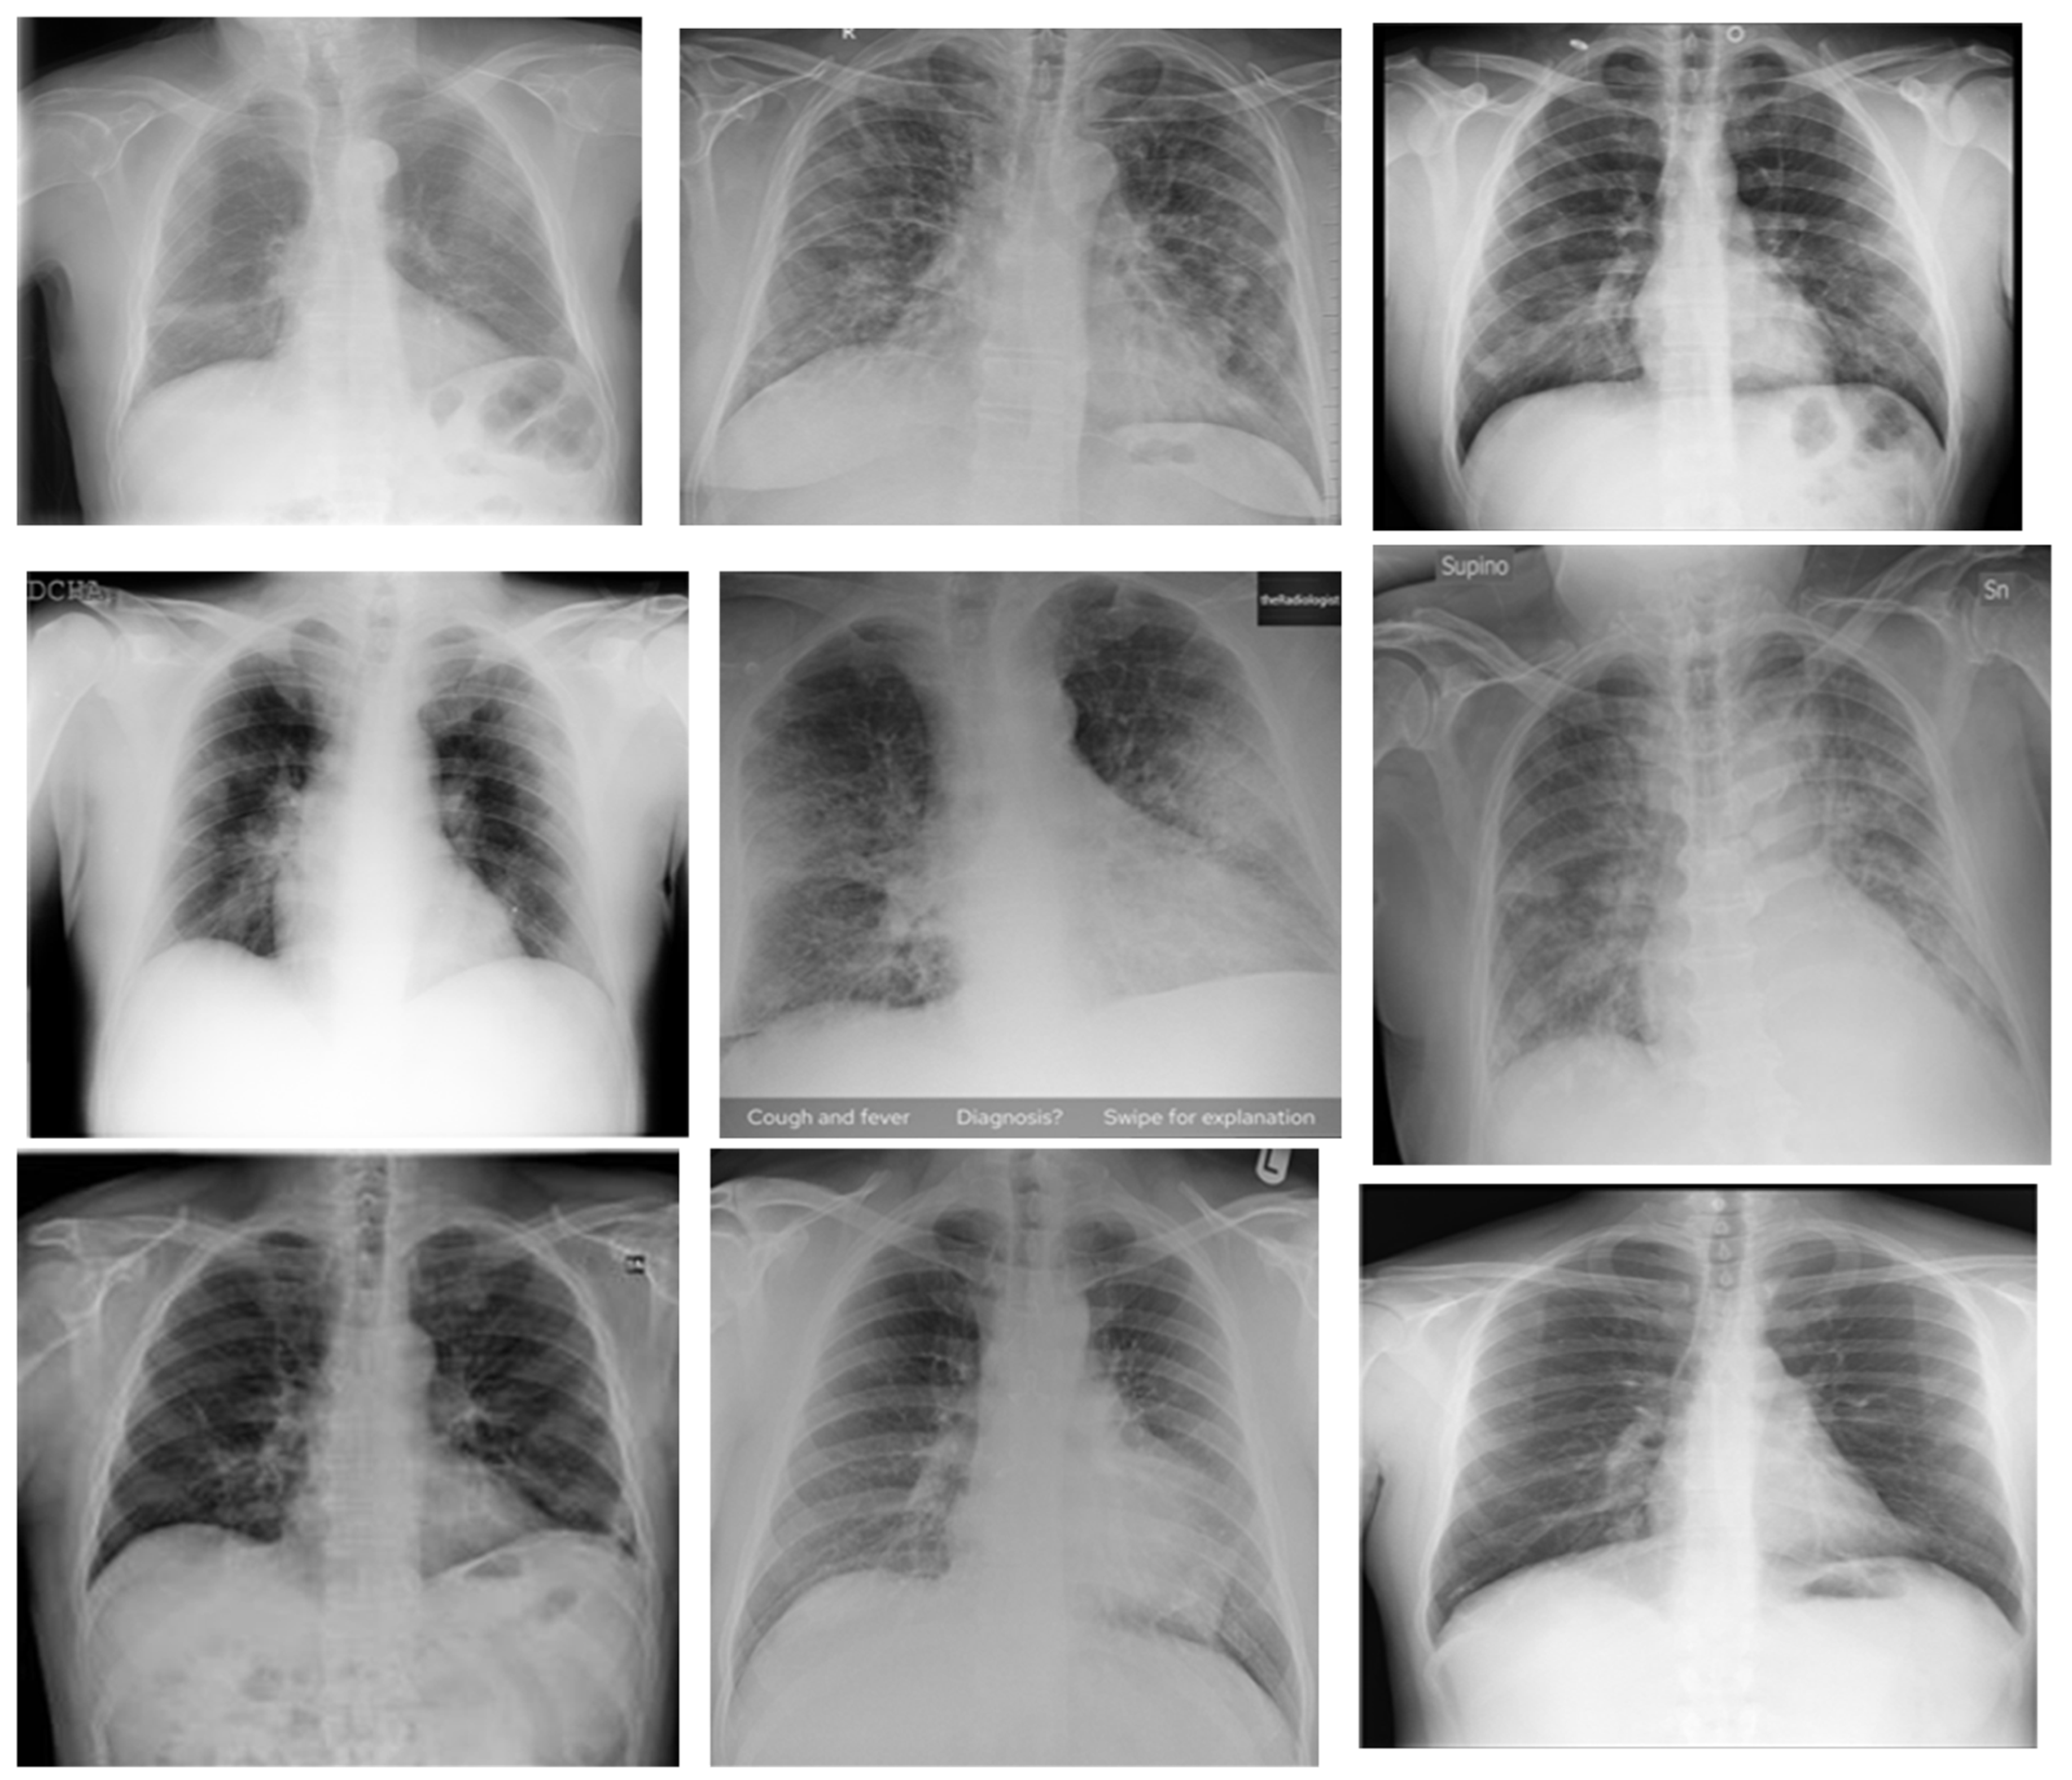

4.2. Experimental Results on X-ray Images

| Proposed System | Major voting classifier is used for reducing the classifier bias. Outcomes of ResNet 50, ResNet100, ResNet101, VGG 16, and VGG 19 are given as input to the major voting classifier. It selects the majority voted one. Image data generator used for synthetic data generation. | Data analysis is one of the modules used in making the system automated. Pre-trained models are used for image analyses. Totally, 7455 CT images and 8900 X-ray images are considered for experimentation. |

| 2200 (images collected from public resource) + 8900 (synthetic data) | X-ray | ResNet 50 | Precision | 82% |

| 2200 (images collected from public resource) + 8900 (synthetic data) | X-ray | ResNet 100 | Precision | 95% |

| 2200 (images collected from public resource) + 8900 (synthetic data) | X-ray | ResNet 101 | Precision | 98% |

| 2200 (images collected from public resource) + 8900 (synthetic data) | X-ray | VGG 19 | Precision | 96% |

| 2200 (images collected from public resource) + 8900 (synthetic data) | X-ray | VGG 16 | Precision | 85% |